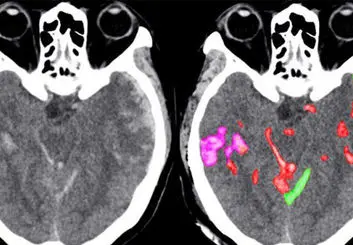

• تشخیص سریع خونریزی مغزی به کمک هوش مصنوعی

تشخیص سریع خونریزی مغزی به کمک هوش مصنوعی